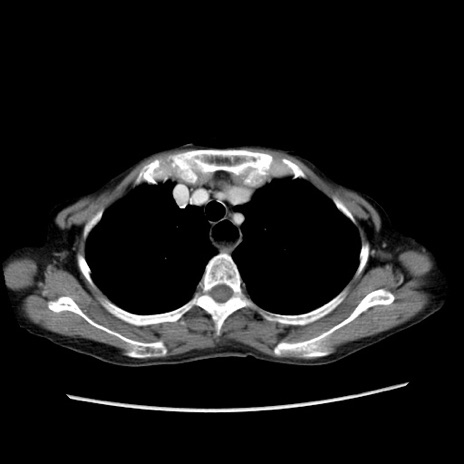

症例25(横断像)

【症例】80歳代女性

【主訴】胸のつかえ感

【現病歴】約9時間前に食後から胸のつかえた感じあり、嘔吐あり、来院。

【既往歴】胃癌(全摘)、胆摘、虫垂炎

【身体所見】心窩部に圧痛あり、反跳痛なし。

【データ】WBC 5700、CRP 0.05